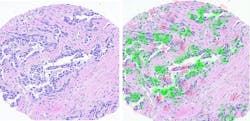

His team first inspected estrogen receptors to determine positive or negative expression status, and whether the computer model could infer this by simply looking at the images (see Fig. 1). “We managed to prove, for the first time, that artificial intelligence can extract information from biopsy images about the molecular profile of the cancer,” Shamai says.This could all tie into immunotherapy, which is treatment that uses a person’s own immune system to fight cancer by attacking tumors and cancerous cells. This type of therapy is personalized so each patient receives the proper medications and care based on specific characteristics of the type of cancer, tumors, and cell receptors. AI/deep learning models will be key to advancing immunotherapy.

The network reviewed breast cancer images from biopsies obtained from Vancouver General Hospital (British Columbia, Canada) to determine which cells expressed the PD-L1 protein and which did not (see Fig. 2). It was able to successfully apply the method to 70% of the patients.Some cases were also reviewed by a human pathologist, who performed the diagnosis and quantified the expression using the advanced immunohistochemistry staining, while the AI predicted the expression without it—in cases where that person and the AI network disagreed, subsequent tests proved the AI findings were correct, because it is able to distinguish certain characteristics that even a highly trained and experienced pathologist simply cannot see.